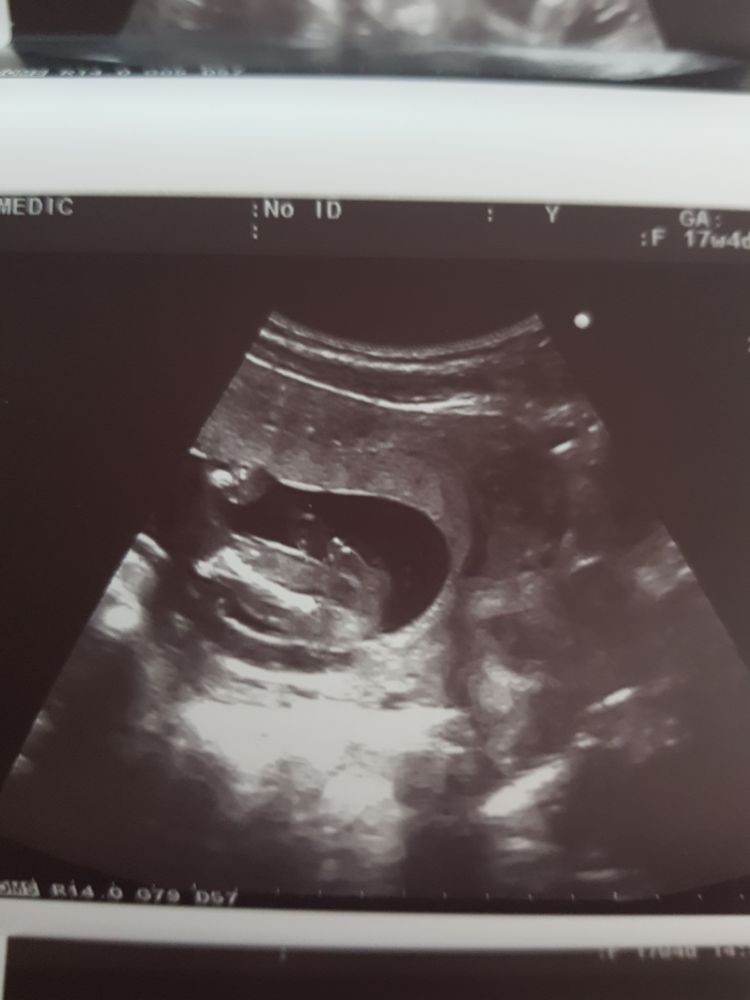

Мальчик :)

Просто что бы оставить себе на память, ну и поделиться с Вами)